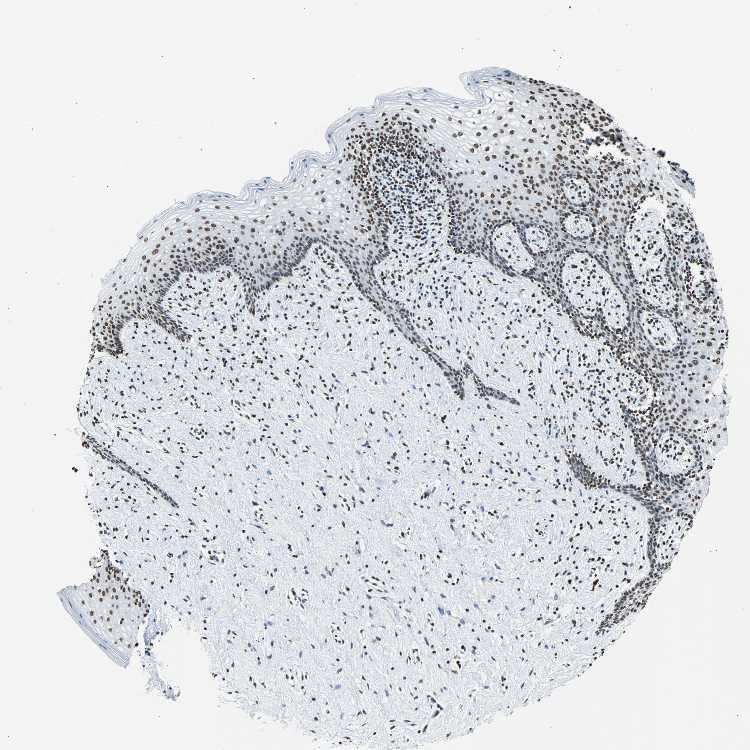

FUBP1